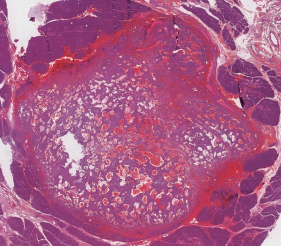

Introducción: El tumor sólido pseudopapilar del páncreas es una rara entidad que representa menos del 1% de las neoplasias pancreáticas. Suele presentarse en mujeres jóvenes y solo da síntomas de carácter compresivo una vez que alcanza un gran tamaño. Dado su comportamiento biologico incierto el tratamiento es la cirugía. Caso Clínico: Presentamos el caso de una mujer de 23 años con historia de 1 año de evolución de dolor epigástrico y baja de peso. El estudio imagenologico demostro una masa heterogenea solida-quistica dependiente de la cabeza del pancreas de aspecto neoplasico. Se realizo una biopsia incisional laparoscopica cuyo resultado fue de un tumor maligno indiferenciado, por lo que se opto por la reseccion quirurgica. Se realizó una pancreatoduodenectomía abierta sin incidentes con un post operatorio favorable. Los análisis histopatológico e inmunohistoquímico fueron compatibles con un tumor sólido pseudopapilar de páncreas.